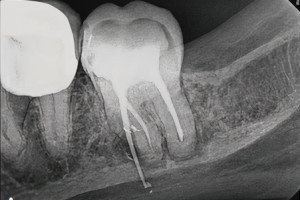

Радиационно-индуцированный некроз или остеорадионекроз характеризуется наличием обнаженной кости после проведения лучевой терапии. Открытая кость может полностью секвестрировать, что часто приводит к обнажению большего количества кости. Хотя кость, расположенная в любом месте челюсти, восприимчива к излучению, задняя часть нижней челюсти поражается чаще, чем другие области, потому что она часто находится в поле излучения, особенно когда в лечение включены лимфатические узлы. Может возникать интенсивная боль при периодическом отеке и дренировании вне полости рта. Однако многие пациенты не чувствуют боли при обнажении костей. Утрата нормальной структуры может нарушить целостность кости, а в некоторых случаях кость может сломаться.